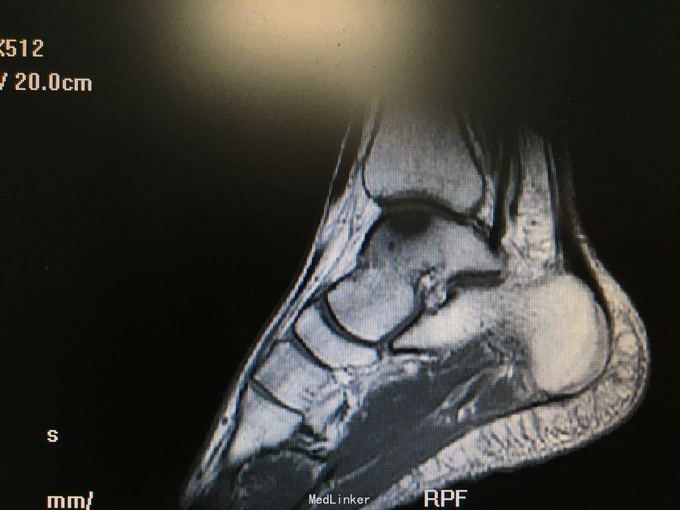

负重时加重,mri示左踝内侧穹隆关节面囊变伴部分坏死

诊断和手术方式如题 直接上图